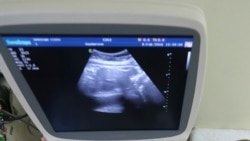

Türkmenistanda ýaňy-ýakynda güýje giren gadaganlyga garamazdan, abort etdirýänleriň sany azalmady we indi köp sanly aýal islenilmeýän göwreliligi aradan aýyrmak üçin para bermeli bolýarlar diýip, aýallar we lukmanlar aýdýarlar.